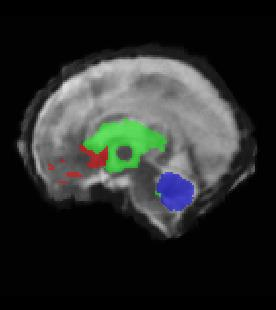

Limiting failures of machine learning systems is of paramount importance for safety-critical applications. In order to improve the robustness of machine learning systems, Distributionally Robust Optimization (DRO) has been proposed as a generalization of Empirical Risk Minimization (ERM). However, its use in deep learning has been severely restricted due to the relative inefficiency of the optimizers available for DRO in comparison to the wide-spread variants of Stochastic Gradient Descent (SGD) optimizers for ERM. We propose SGD with hardness weighted sampling, a principled and efficient optimization method for DRO in machine learning that is particularly suited in the context of deep learning. Similar to a hard example mining strategy in practice, the proposed algorithm is straightforward to implement and computationally as efficient as SGD-based optimizers used for deep learning, requiring minimal overhead computation. In contrast to typical ad hoc hard mining approaches, we prove the convergence of our DRO algorithm for over-parameterized deep learning networks with ReLU activation and a finite number of layers and parameters. Our experiments on fetal brain 3D MRI segmentation and brain tumor segmentation in MRI demonstrate the feasibility and the usefulness of our approach. Using our hardness weighted sampling for training a state-of-the-art deep learning pipeline leads to improved robustness to anatomical variabilities in automatic fetal brain 3D MRI segmentation using deep learning and to improved robustness to the image protocol variations in brain tumor segmentation. Our code is available at https://github.com/LucasFidon/HardnessWeightedSampler.